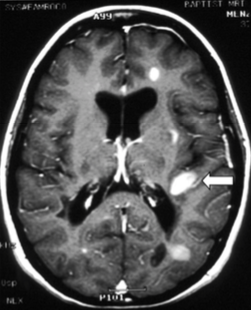

How is IV gadolinium used in MS mgmt?

What do you see here?